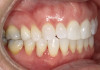

A 52-year-old female patient with history of lost retainers that she had used for a previous orthodontic treatment presented with minor orthodontic relapse during a hygiene visit. Her chief concern was that her lateral incisors were "starting to flare forward," as she had not been compliant with her retainers, and she expressed a desire for an affordable clear aligner solution. Clinically she presented with upper and lower anterior tooth crowding of less than 3 mm, specifically lower anterior teeth Nos. 23, 24, and 25, with a reverse curve of Spee of less than 2 mm on the lower anterior teeth (Figure 1 through Figure 3). The upper anterior arch presented with lateral incisor buccal rotations of less than 15 degrees on teeth Nos. 7 and 10 from an overjet view (Figure 4). The patient's oral hygiene was within normal limits, with stage one gingivitis, based on the new multidimensional staging and grading system of the American Academy of Periodontology and the European Federation of Periodontology that was adopted in 2017.12 The patient also presented with class I bite classification with gingival abfraction on both the anterior and posterior arches, with visibly missing class V restorations (Figure 5 and Figure 6).

Fig 2. Patient presented with upper and lower anterior tooth crowding

of less than 3 mm. Figure 1: Anterior view. Figure 2: Upper arch. Figure 3: Lower

arch.

Figure 2